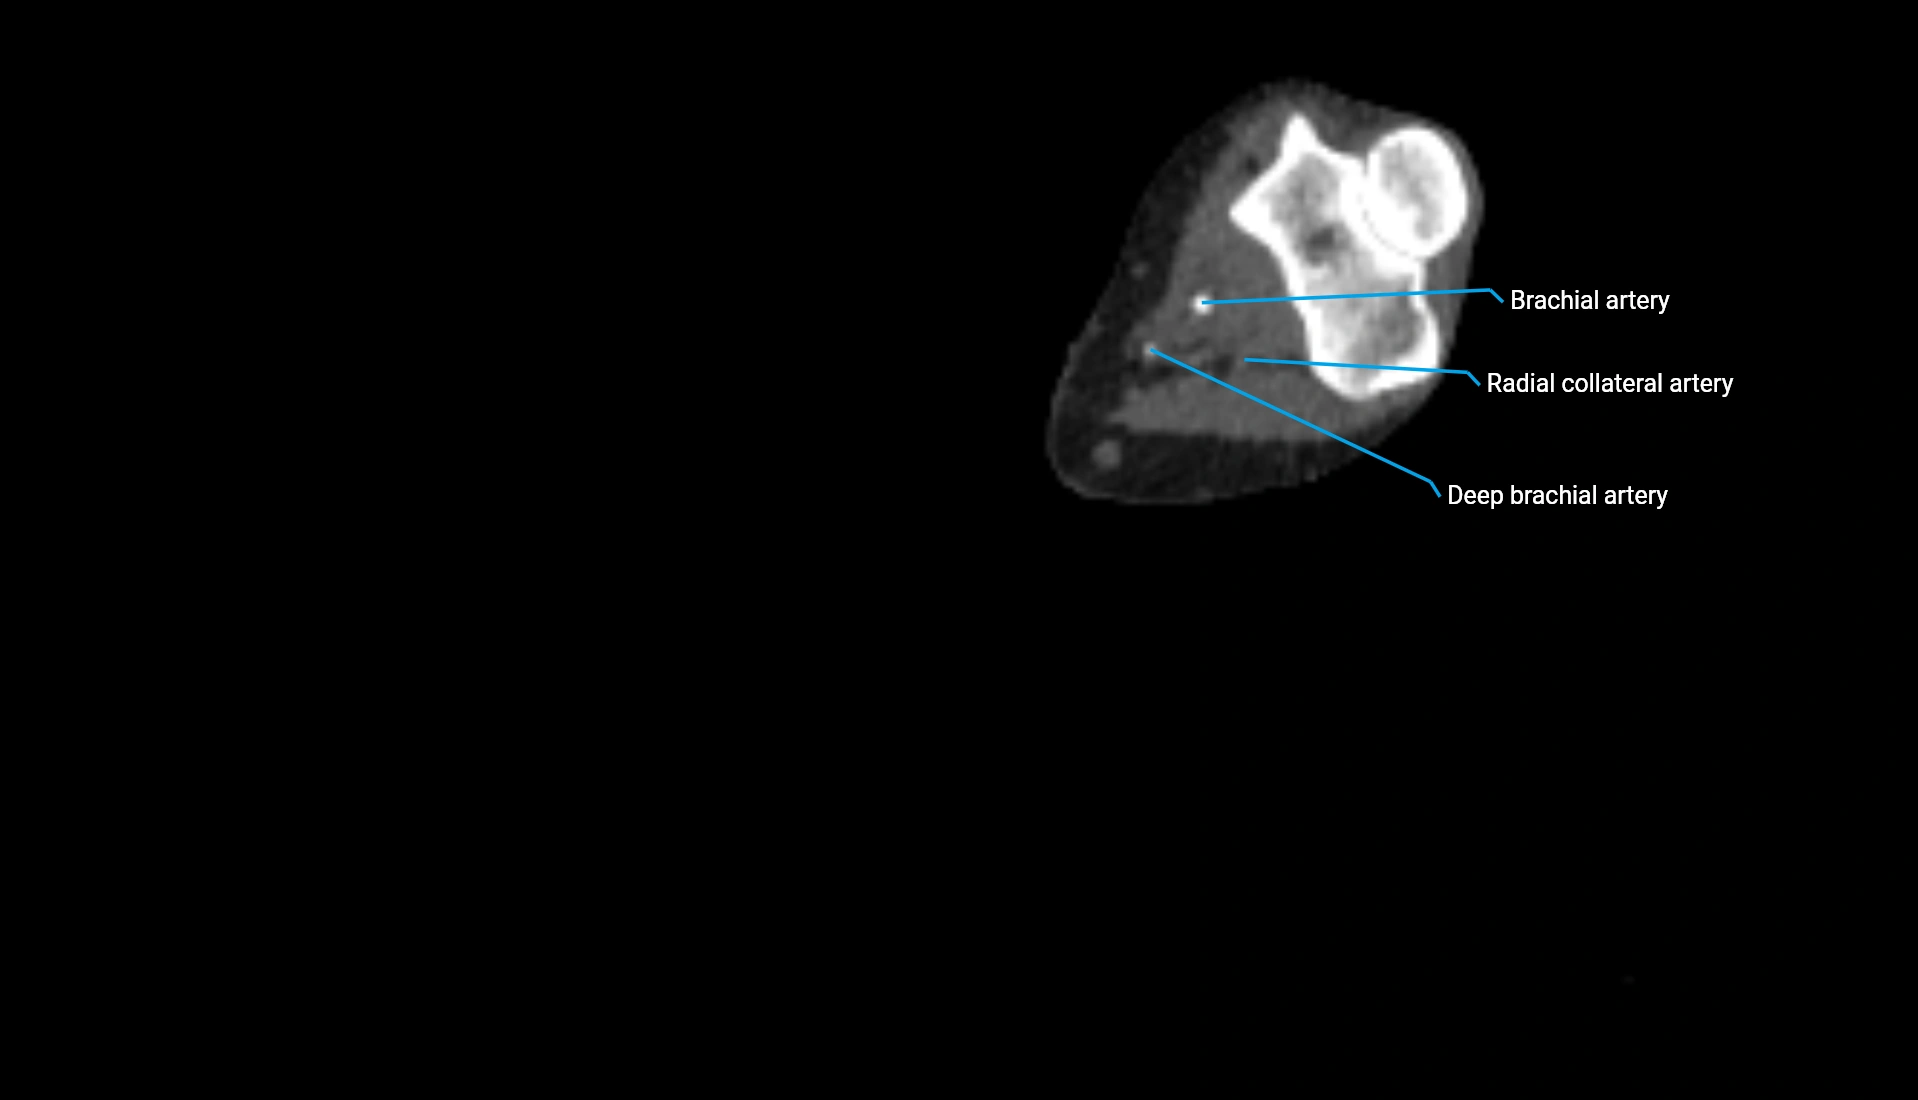

CT Appearance

Non-Contrast CT:

• Cortex: High-density, sharply defined

• Subchondral bone: Dense cancellous matrix

• Articular surface: Smooth concave contour articulating with the capitellum

• Excellent for evaluating bone integrity, alignment, and subtle fractures